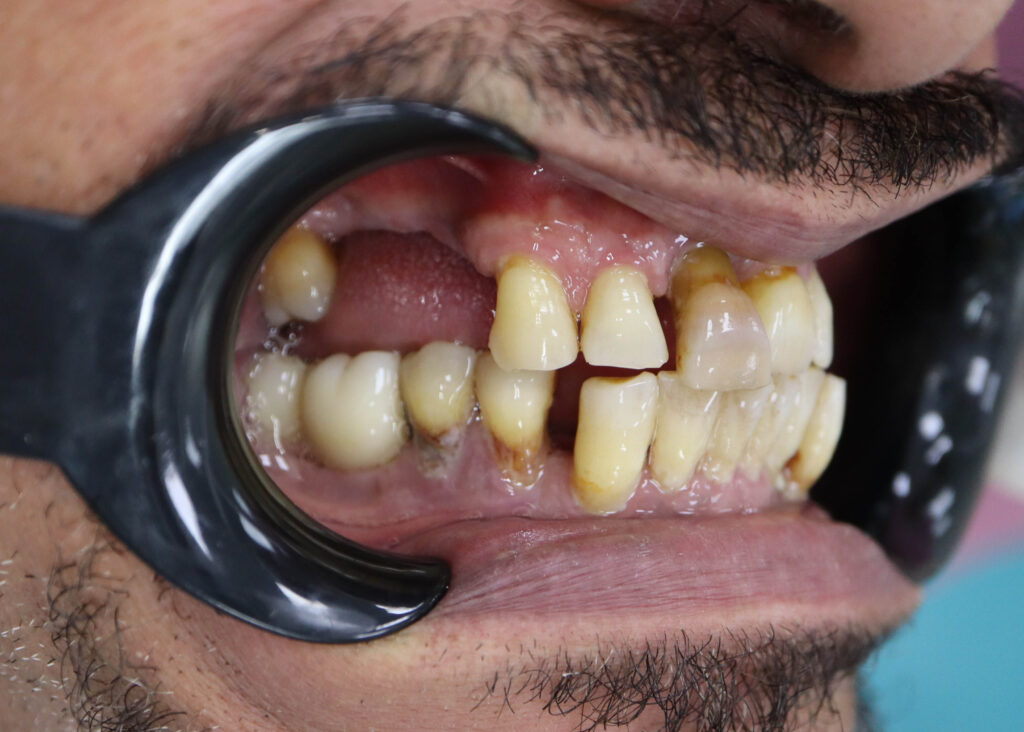

Ситуация до лечения

Пациент обратился с жалобами на эстетические недостатки.

У пациента уже стояло некоторое количество имплантатов. Было решено использовать их при протезировании.

пациент до имплантации